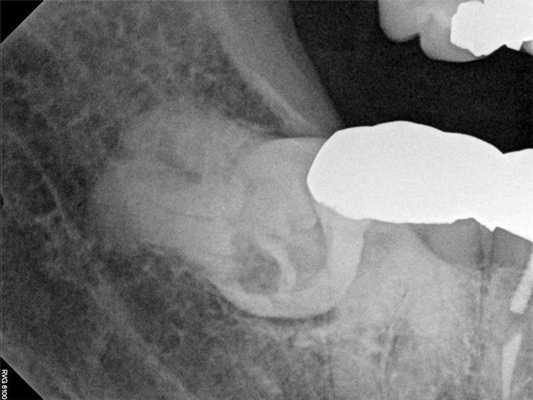

Чтобы купировать выраженные болевые ощущения пациента была проведена блокада нижнего альвеолярного нерва посредством 3,4 мл 0,5% раствора бупивакаина с концентрацией эпинефрина 1:200000. Через 5 минут после анестезии пациент сообщил о полном разрешении боли. Учитывая факт купирования болевых симптомов после выполнения анестезии, было предположено, что этиология таковых является одонтогенной. В ходе выполнения повторной рентгенографии была визуализирован участок внутрикоронковой резорбции непрорезавшегося 32 зуба. Пациент был направлен к челюстно-лицевому хирургу с целью удаления проблемного зуба. После экстракции больной сообщил, что все симптомы боли разрешились. После выполнения экстракции был подтверждён диагноз внутрикоронковой резорбции 32 зуба.

Фото 4. Клинический случай 1. После выполнения анестезиологической блокады было проведенного повторное рентгенологическое обследование, которое позволило обнаружить внутрикорональную резорбцию в структуре ретинированного моляра, которая спровоцировала развитие симптомов необратимого пульпита.